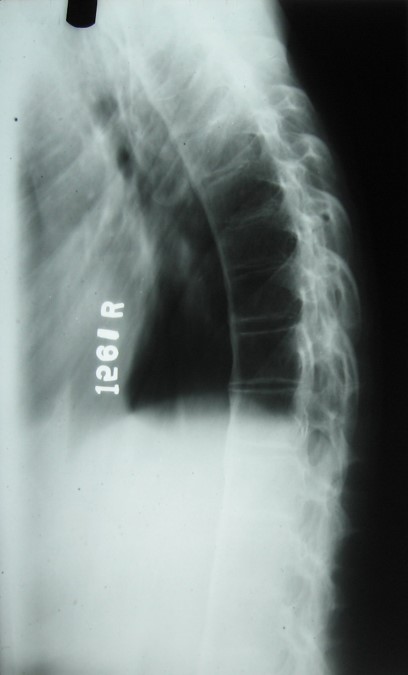

Thoracic Spine Lateral – same patient